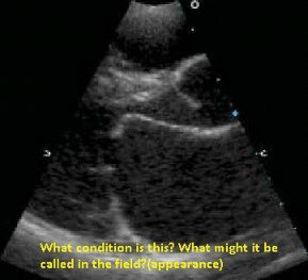

RVVO |